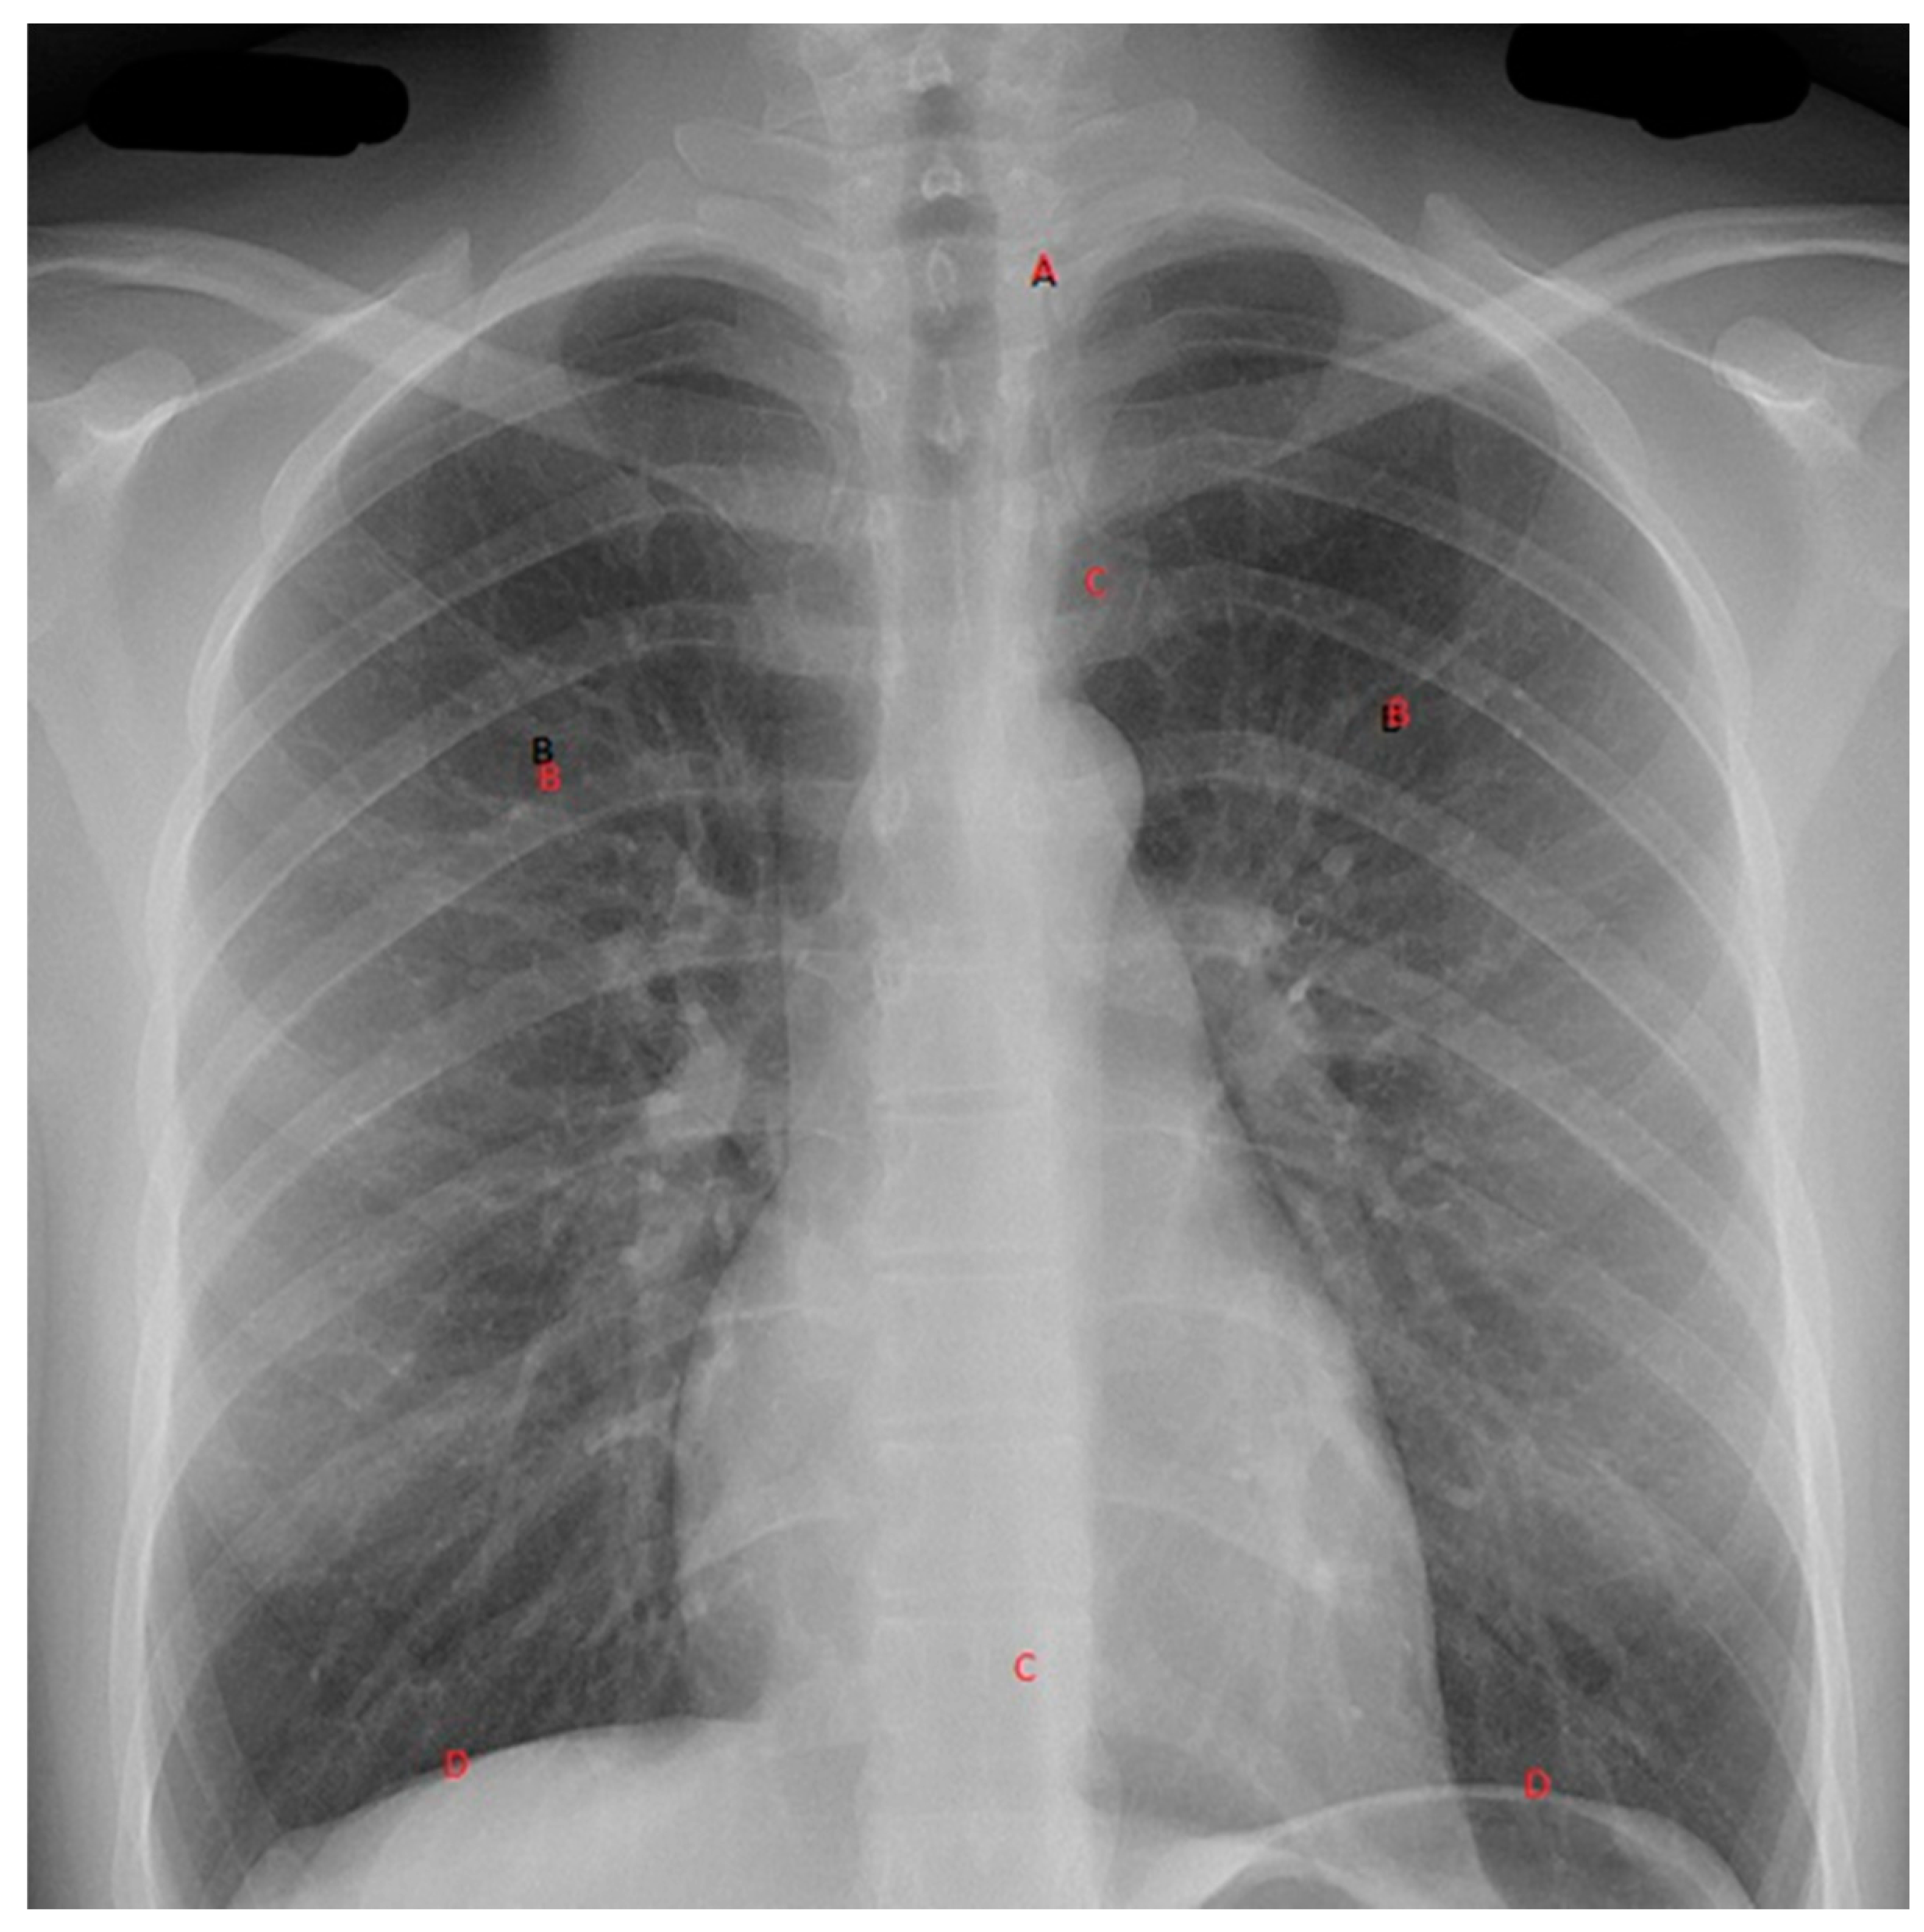

With these devices comes the need to ensure reliable interpretation of the images obtained. Adopting a clinician-based reporting system to assess radiographs will allow interpretation of these x-rays to optimise identifying pathology and minimise missed diagnosis. For C-spine x-rays: in interpreting a lateral c-spine x-ray the following system may be adopted: adequacy (C1 to top of T1), check alignment along four lines namely A Anterior vertebral line, B Anterior spinal line, C Posterior spinal line, D Spinous processes. For the Chest X-ray a recommended system for interpreting a plain AP Chest x-ray would be following an ABCDEF approach (illustrated in Figure 3): Airway: position of trachea and of endotracheal tube if present; Breathing: Lung field assessment looking specifically for: Haemothorax, Pneumothorax, Contusion Circulation, Mediastinal width, Heart shape and size; Diaphragms and any Extras : any extra visible eg: ECG electrodes, Nasogastric tube etc. Finally look for Fractures: follow a system from medially to laterally: Ribs (anterior and posterior), Clavicle, Scapulae Humerus, Vertebrae if visible. A similar system can be used for the pelvis, limbs and the vertebrae plain X-rays as well.

Figure 3. The ABDCEF approach to viewing a chest x-ray.